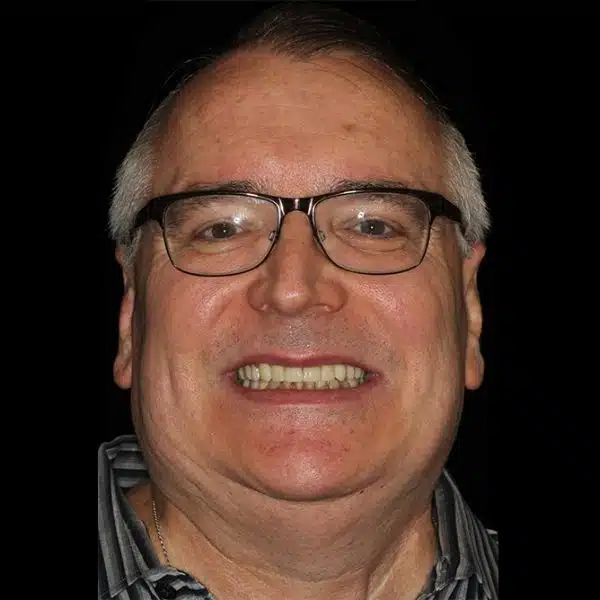

Photos of Crown and Bridge Treatment are posted below. Board-certified prosthodontist, Dr. Glenn Wolfinger from Pi Dental Center, completed full-contour Zirconia Fixed Bridges in the lower posterior teeth, and full-contour Zirconia Crowns on the upper teeth.

The crowns were completed using TRIOS® digital scan technology.

Prosthodontic Treatment: Glenn J. Wolfinger, DMD, FACP

Final Restorations: Stephen F. Balshi, MBE (CM Prosthesis)

Lab Work: The provisional crowns and bridges were created by certified lab technician, Antionette Robinson. The final crowns and bridges were created by Stephen F.Balshi, MBE of CM Prosthetics and Pi Dental Center Ceramist, Nancy Gausz, who applied porcelain to the front of the teeth for improved esthetics.